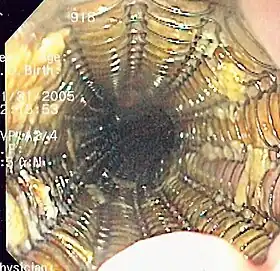

Endoscopic polypectomy has been carried out since the early 1970s by both endoscopic snare removal and fulguration of polyps with hot biopsy forceps.[15][16]